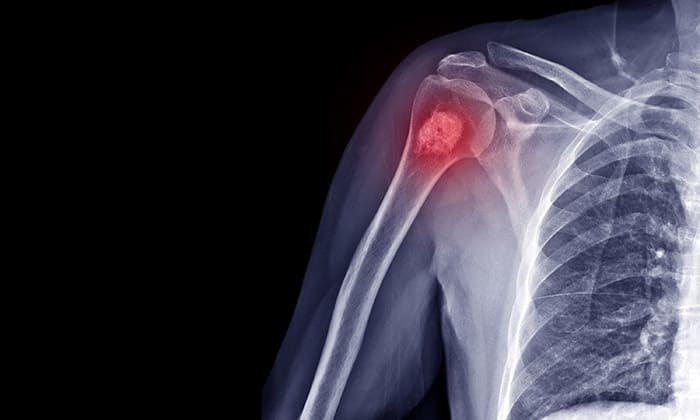

เนื้องอกกระดูกอ่อน (Enchondroma) คือโรคเนื้องอกกระดูกชนิดหนึ่งที่ไม่ใช่เซลล์มะเร็ง มีจุดเริ่มต้นเนื้องอกในบริเวณกระดูกอ่อน เนื้อเยื่อเกี่ยวพันชนิดหนึ่งในร่างกายที่พบได้ในบริเวณข้อต่อต่าง ๆ หู จมูก และหลอดลม เป็นต้น เนื้องอกกระดูกอ่อนน้นมักจะเกิดขึ้นพร้อมกับกลุ่มอาการที่เรียกว่า กลุ่มอ่าการ Ollier’s and Mafucci’s syndrome

โดยส่วนใหญ่แล้ว เนื้องอกกระดูกอ่อนนี้มักจะเกิดขึ้นกับกระดูกอ่อนที่อยู่ภายในกระดูก และมักจะเกิดขึ้นกับกระดูกส่วนเล็ก ๆ เช่น กระดูกที่มือ หรือกระดูกที่เท้า แต่ก็สามารถเกิดขึ้นกับกระดูกอ่อนส่วนอื่น ๆ ได้เช่นกัน

• เอกซเรย์ เพื่อฉายภาพให้เห็นภายในร่างกาย ว่ามีความผิดปกติ หรือเนื้องอกตรงไหนหรือไม่

• ซีทีสแกน (CT scan) เป็นการตรวจโดยใช้รังสีเอกซเรย์เพื่อฉายภายในร่างกายให้เห็นได้ชัด โดยเฉพาะในบริเวณกระดูก กล้ามเนื้อ ไขมัน และอวัยวะต่าง ๆ ทำให้แพทย์สามารถมองเห็นเนื้องอกหรือความผิดปกติบริเวณกระดูกอ่อนได้ชัดเจนขึ้น